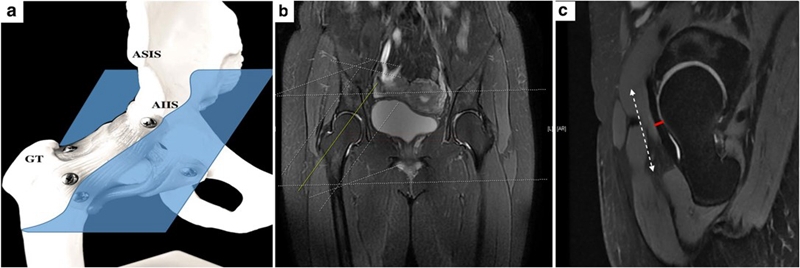

前关节囊除了进行X线指标的测量之外,我们尤其关注了厚度,测量方法选择在斜矢状位上,在整个前关节囊的中段进行了厚度的测量。见图9C中红色线段部位。

术前磁共振测量的案例